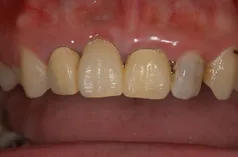

[症例①]

![[症例①]](/wp-content/uploads/unnamed-1.png.webp)

![[症例①]](/wp-content/uploads/unnamed-2.png.webp)

前歯4本をCAD/CAMで作製した冠で治療した症例です。

右の前歯(向かって左の前歯)は欠損しているので、ブリッジになっています。

冠の色調もきれいですが、オールセラミック・クラウンを使用することで光が透過し、歯の付け根の歯肉の色調も明るくきれいになります。

加齢とともに歯肉が痩せても、金属が見えることはありません。

- 治療費(税込): 66万円

- 治療期間: 3ヶ月

- 治療回数: 5回

- メリット: 見た目が綺麗で自然

- 副作用(デメリット): 術後のメンテナンスを定期的に行う必要がある